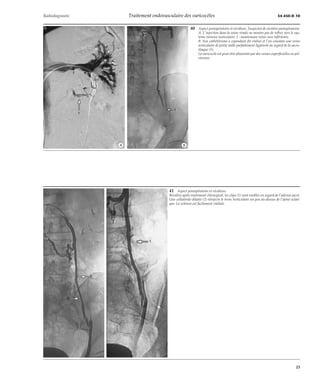

36 Technique de traitement. La sonde n’a pas pu être descendue en dessous de l’aile-ron

sacré, il a été mis en place un ressort (flèche). Puis un guide-cathéter (1) a été placé

bas de façon à compléter cette première thérapeutique par la sclérose.

37 Technique de traitement. Mise en place de deux ressorts, assez bas, dans une veine

testiculaire d’assez grande taille.

38 Technique de traitement. Très volumineuse veine testiculaire ayant incité à la

mise en place de deux ressorts de grande taille.

39 Technique de traitement. Mise en place dans deux branches pelviennes, à deux ni-veaux

différents, de trois ressorts (flèches).